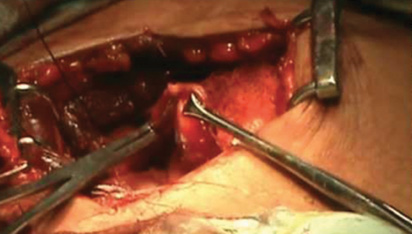

La nota quirúrgica de las 1:20 h del 19 de mayo de 2013 estableció: hallazgo de múltiples adherencias pared asa, múltiples abscesos de pared, uno interasa, líquido purulento en hueco pélvico y región subhepática, apéndice cecal necrosado y perforado; se realizó apendicectomía con abordaje laparoscópico y lavado de cavidad.

Relacionado con la cirugía efectuada a la paciente, la parte actora presentó entre sus pruebas un disco compacto con la videograbación del procedimiento quirúrgico. Esta prueba demostró plenamente que durante el procedimiento laparoscópico, en ningún momento se mostró pus libre en cavidad peritoneal, ni abscesos de pared o interasa, existiendo sólo adherencias laxas, constituidas por fibrina y natas fibrinopurulentas conglomeradas en un plastrón, conformado por asas de intestino delgado y epiplón a nivel de la válvula ileocecal.

La citada prueba mostró apéndice cecal hiperémico, hipervascularizado, íntegro, con natas fibrinopurulentas en la superficie externa (serosa), principalmente en su punta, sin evidencia de necrosis, lisis o perforación apendicular. También mostró que al extraer el apéndice seccionado por contraabertura, existió fuga de contenido apendicular a la cavidad, pues las grapas colocadas en el segmento proximal del apéndice no obstruyeron completamente su luz. Es necesario precisar, que para evitar una fuga, se debe colocar el apéndice en una bolsa, lo cual no ocurrió en este caso.

En esos términos, los hallazgos reportados por el cirujano pediatra en su nota quirúrgica, no coinciden con lo demostrado mediante la videograbación del procedimiento quirúrgico.

Lo anterior fue reforzado por el estudio histopatológico de la pieza quirúrgica, el cual reportó apendicitis abscedada y periapendicitis, y confirma que el apéndice cecal extraído no presentó datos de necrosis, lisis o perforación, y que por las características macroscópicas (natas fibrinopurulentas), se trató de un proceso apendicular fase II, que equivale a apendicitis fibrinopurulenta, sin necrosis ni perforación.